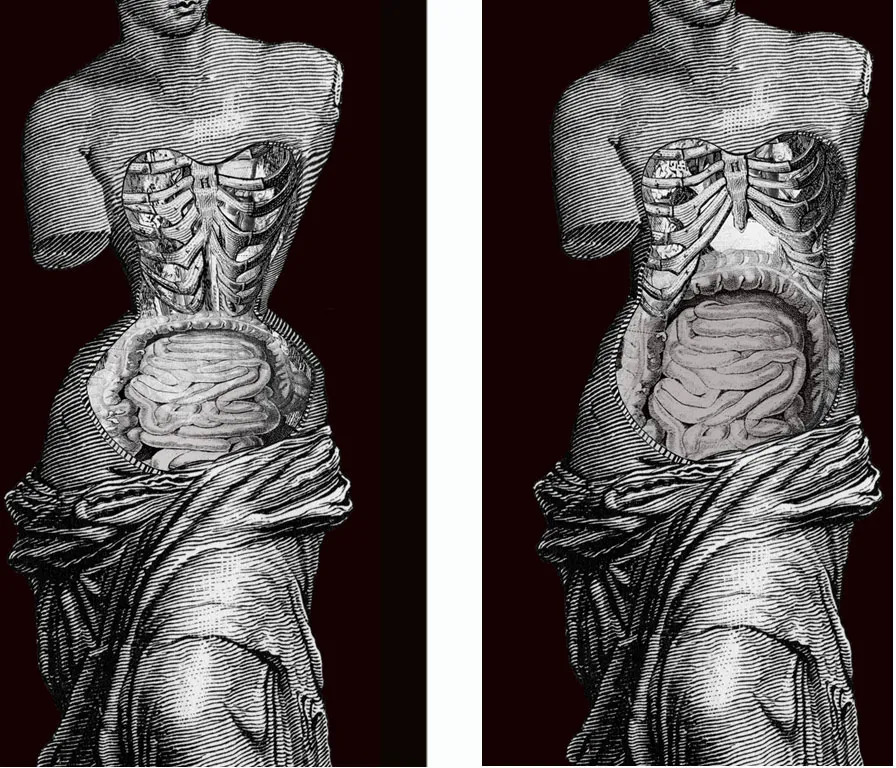

历史上束腰第一次在潮流中逐渐暗淡,就归功于每年数篇讨论束腰不利于内脏健康的论文。它会压迫内脏,引起胃酸返流。

束腰对内脏的压迫;图/Valencian Museum of Ethnology

尽管现代束腰——塑形内衣通过各种术语试图改变这种印象,比如声称使用了新型材料和技术等,医学对塑形内衣造成生理和心理危害的警告依然存在,神经痛、消化困难、静脉曲张、血栓等病症名列塑形内衣生理风险的头几位。